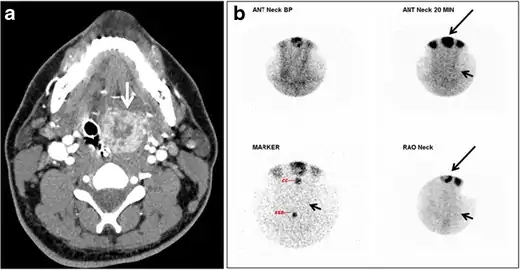

| CT scan and scintigraphy images of lingular ectopic thyroid | |

An ectopic thyroid, also called accessory thyroid gland, is a form of thyroid dysgenesis in which an entire or parts of the thyroid located in another part of the body than what is the usual case. A completely ectopic thyroid gland may be located anywhere along the path of the descent of the thyroid during its embryological development, although it is most commonly located at the base of the tongue, just posterior to the foramen cecum of the tongue. In this location, an aberrant or ectopic thyroid gland is known as a lingual thyroid.[3] If the thyroid fails to descend to even higher degree, then the resulting final resting point of the thyroid gland may be high in the neck, such as just below the hyoid bone.[3] Parts of ectopic thyroid tissue ("accessory thyroid tissue") can also occur, and arises from remnants of the thyroglossal duct, and may appear anywhere along its original length.[3] Accessory thyroid tissue may be functional, but is generally insufficient for normal function if the main thyroid gland is entirely removed.[3]